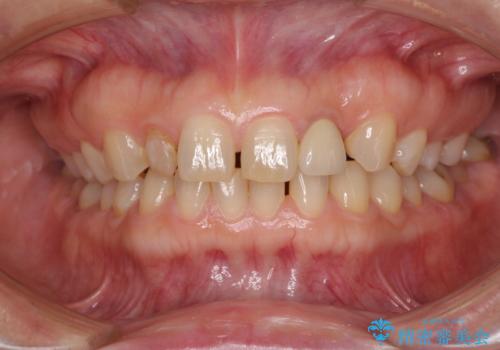

- 前歯の矮小歯に貼り付けられていたラミネートベニアが外れてしまったとのことで来院された患者様です。

反対側の矮小歯は裏打ちが金属であったため、両方の歯ともにオールセラミッククラウンにて補綴することとしました。

前歯の隙間や、周りの歯と色合いの違いなどはあまり気にしていらっしゃらなかったため、矮小歯の2歯を自然な大きさに仕上げました。

とても自然な歯が装着されたとのことで、患者様には大変満足していただきました。